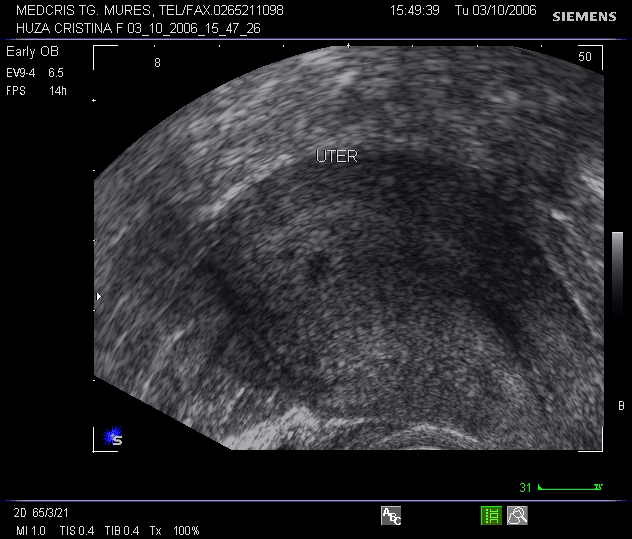

ECOGRAFIA TRIMESTRULUI I DE SARCINA

Ecografia trimestrului I de sarcina Indicatiile ecografiei: [ 1,3,4,5] 1. confirmarea sarcinii si a viabilitatii 2. sangerarea pe cale vaginala in sarcina 3.Citeste tot ... 1322 cuvinte

Dimensiune mica + cu imagini |